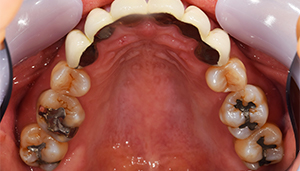

治療前:上の歯

担当医師所見:

臼歯部に残根状態の歯牙があり、またカリエス(虫歯)の散在が認められる。残根部分の両隣在歯は欠損部に対して傾斜し始めている。

治療後:上の歯

左上第1大臼歯は抜歯し、仮歯に置き換えた後治癒を待ちジルコニアBrで補綴。また右上第1大臼歯は根管治療終了後にジルコニアクラウンで補綴。前歯部は審美性を考慮しジルコニアボンドにて補綴した。 色調、形態共に調和がとれている。